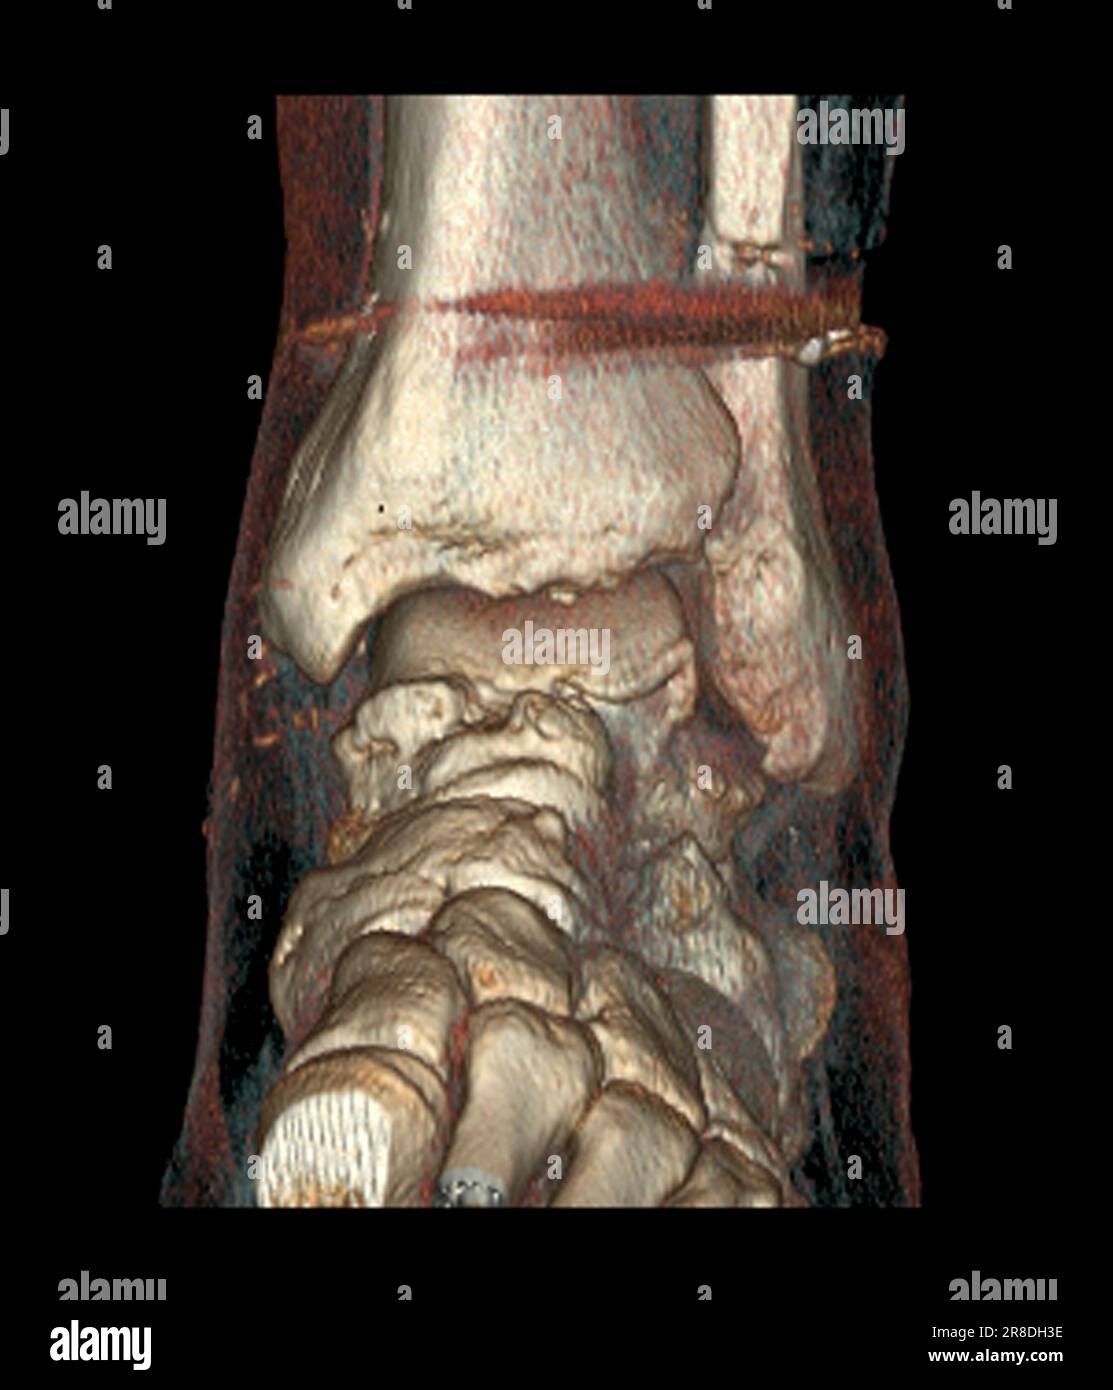

From www.alamy.com

Coloured 3D computed tomography (CT) scan of the pinned ankle of a 32 Calf In Bone Fracture The proximal tibia is the upper portion of the bone where it widens to help form the knee. Fibula fractures occur around the ankle, knee, and middle of the leg. A broken leg (leg fracture) is a break or crack in one of the bones in your leg. Here, health care providers typically evaluate the injury and immobilize the leg. Calf In Bone Fracture.

Coloured 3D computed tomography (CT) scan of the pinned ankle of a 32 Calf In Bone Fracture The fibula, or calf bone, is a small bone located on the outside of the leg. Here, health care providers typically evaluate the injury and immobilize the leg with a splint. Healthcare providers also call broken legs fractured legs. There are three bones in your leg, including. A fibula fracture describes a break in this bone. Treatment can vary, but. Calf In Bone Fracture.